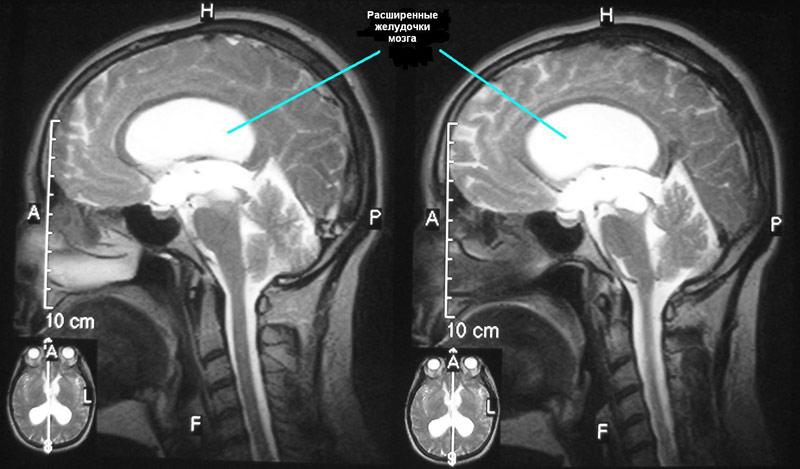

С помощью магнитно-резонансной томографии определяют стадию гидроцефалии, ее причину, форму.